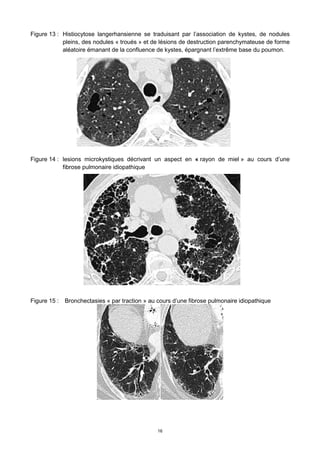

Figure 8 : Lymphangite carcinomateuse. Radiographie thoracique montrant un syndrome réticulo-

nodulaire. Scanner en haute résolution (coupes passant par l’apex et par la base du

poumon gauche) montrant un épaississement des septa inter-lobulaires (SIL)

dessinant la périphérie des lobules pulmonaires (les flèches désignent des artères

centro-lobulaires).

Figure 9 : Réticulations intra-lobulaires dans le cadre d’une pneumopathie interstitielle non

spécifique (PINS).